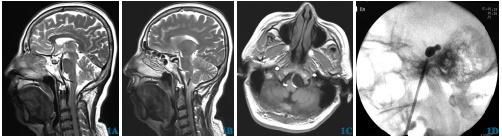

行PBC,术中穿刺针经卵圆孔进入Meckel腔时,心率由90次/min骤降至70次/min,表现为起搏心率,术毕心率恢复至80次/min左右。术中可见球囊呈典型梨形形态,术中效果满意,压迫150s后撤出球囊。术后病人痛感即刻消失,持续心电监测均为窦性心律。次日出院。2d后返院诉面部麻木、咀嚼肌无力,3个月后症状缓解,期间疼痛无再发。

图1 经皮穿刺微球囊压迫术治疗三叉神经痛诱发窦性停搏病人。1A、1B术前MRI矢状位;1C术前MRI轴位,可见迂曲椎动脉压迫延髓;1D术中可见球囊呈典型梨形